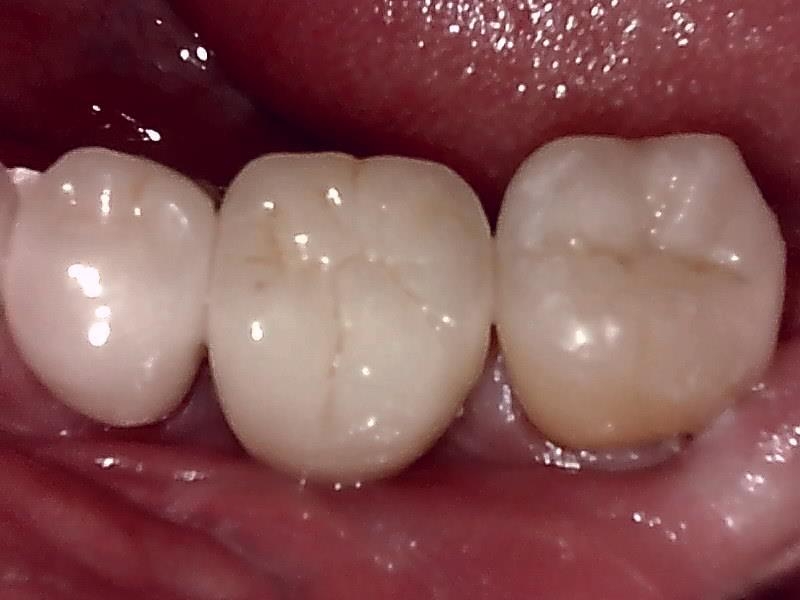

インプラントの上部構造 (左下)

(ジルコニアセラミッククラウン)

術後、とても経過良好です。